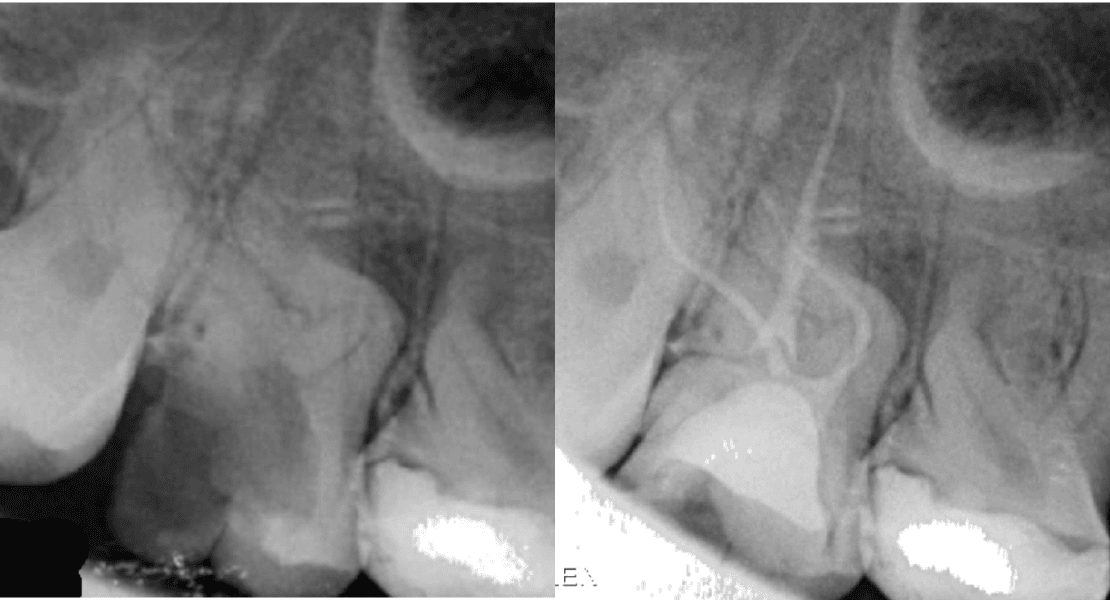

🥈 Dt. Barkın Aksu

Aşırı Kurvatürlü Maksiller İkinci Molar (Diş 17) Tek Seans Kök Kanal Tedavisi ve Endokron Restorasyonu